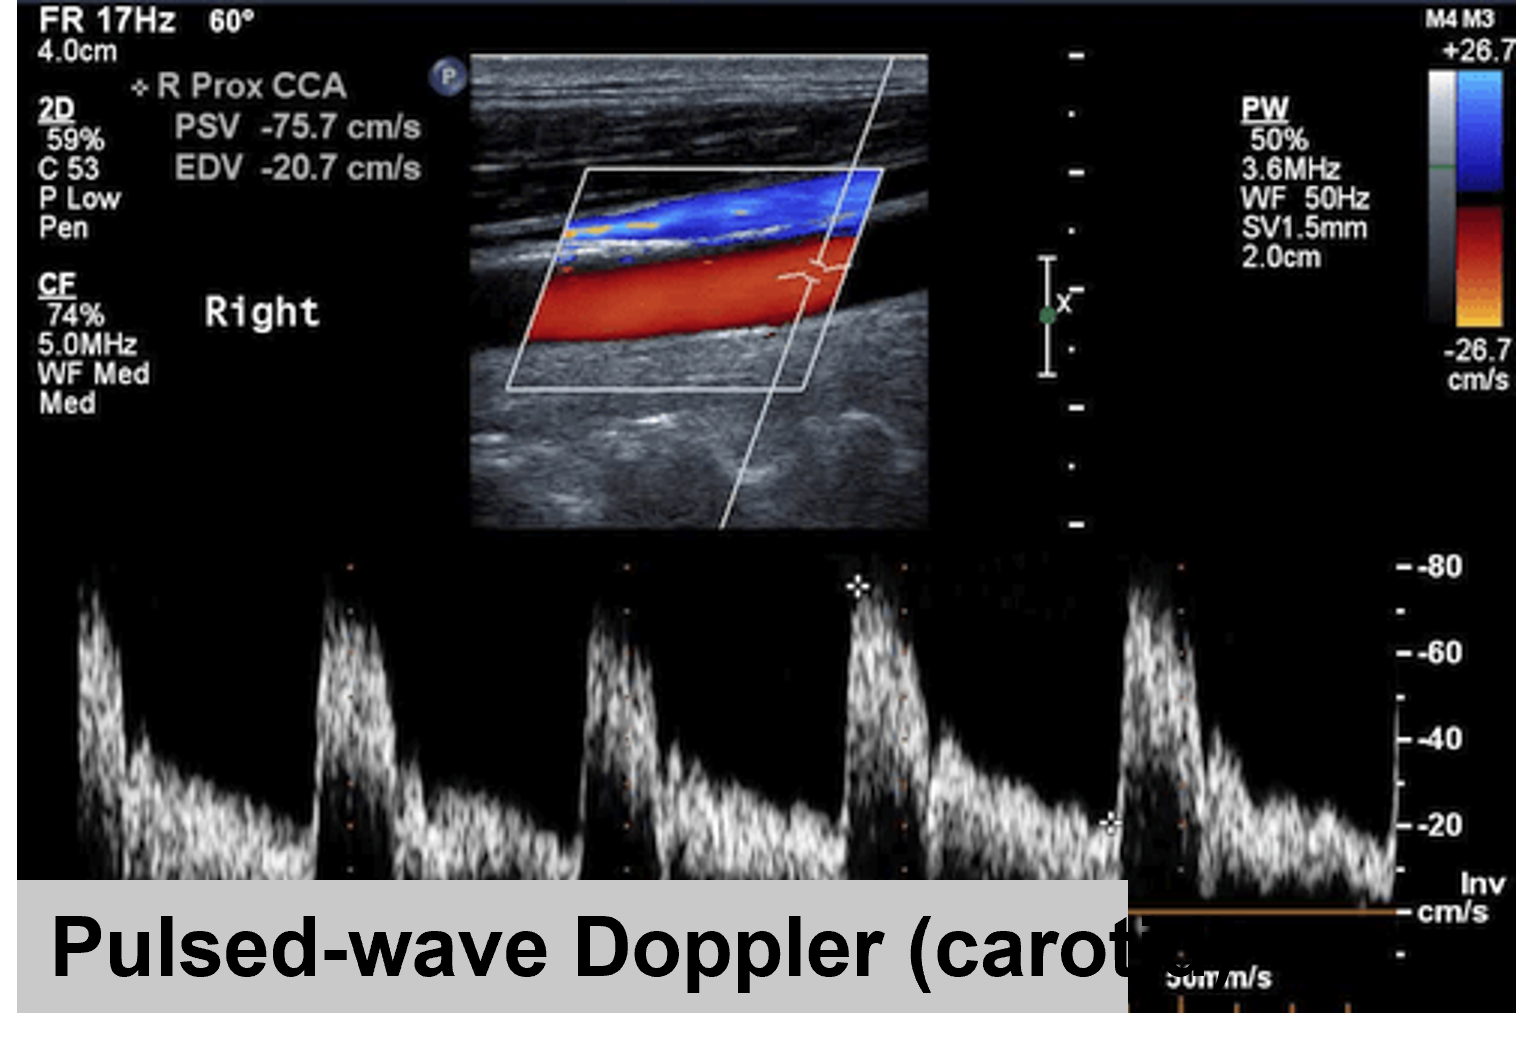

Pulsed Wave Doppler

Pulse Wave Doppler is one of the two methods of Spectral Doppler, recording the blood velocity from a sampling volume. In Pulsed Wave Doppler, the user defines a small area (the sample “volume” or “gate”) within the B-mode image, and the Doppler shifts from that area are recorded. The intermittent sampling of pulsed wave Doppler renders the modality vulnerable to aliasing at higher velocities, especially for distant target areas.

Figure 1. Pulsed-Wave Doppler in the carotid common artery (CCA)